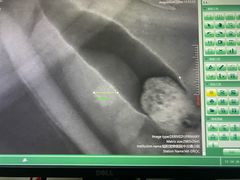

• 美联众合宠物医院·爱萌分院·内外科·猫科中心

• -美联众合宠物医院·爱萌分院·内外科·猫科中心